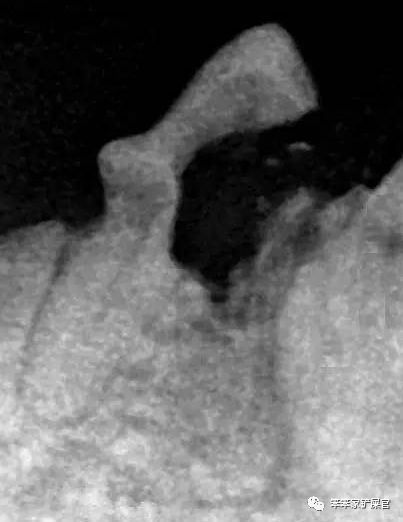

▲图为二型的典型案例

这种类似经常会出现表面看似没问题,但实际上牙根早就已经被侵蚀的情况~